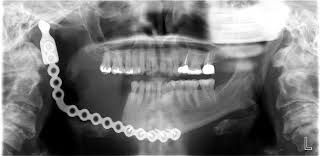

The procedure takes anywhere from seven to nine hours. It begins with removing all the dead bone on that side of jaw. I will lose the next two teeth in line as well since they are sitting on top of dead bone. Fortunately the titanium plate (pictured above) then implanted will not, in my case, pass the mid-line, as in this stock picture I grabbed from the web. While the oral surgeon does his thing up above, a micro-vascular surgeon will work below on my right thigh to start something called a “free flap” transplant. When the jaw is finished, then the second surgeon will attach the vein he pulls from my leg to a good blood supply on the left side of my neck and run it across to the right side. This will insure adequate blood supply for the needed tissue growth and healing of the jaw.